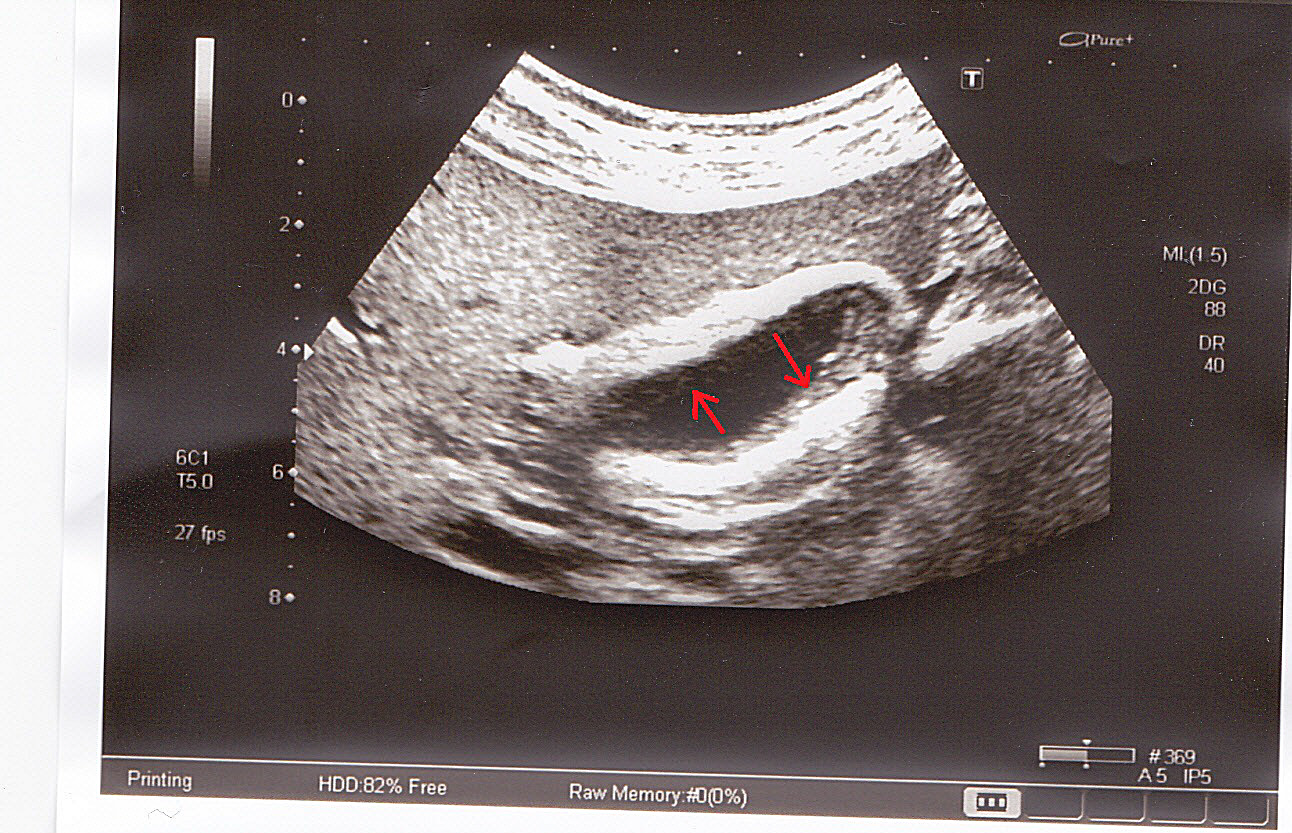

очаги в селезенке

Молодая женщина,38 лет. При прохождении медкомиссии предъявляет жалобы на боли в эпигастрии, плохой аппетит. В анализах гемоглобин 101, СОЭ- 42,что послужило причиной направления на УЗИ. По органам без очаговой эхопатологии,забрюшинные л.у. не увеличены. а вот в селезенке множество ...